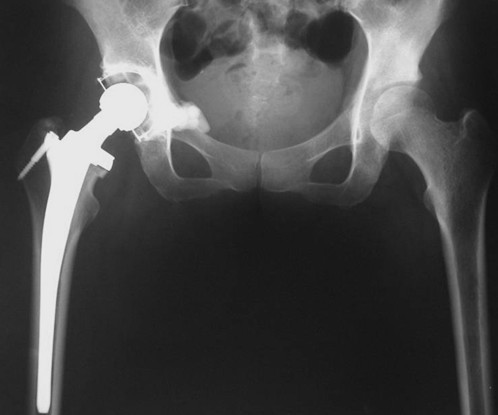

本组病例中不同部位髋臼转移癌的手术方式(图1):I型:髋臼下壁骨破坏、上壁及内、外侧壁完整, 采用肿瘤刮除、普通水泥型全髋置换术。II型:髋臼内、外侧壁破坏,上壁骨质完整, 采用带翼网杯+水泥型全髋置换术。 III型:髋臼上壁及内、外侧壁均破坏,采用肿瘤刮除后、骨水泥填充髋臼上壁骨缺损,带翼网杯+水泥型全髋或组合式人工半骨盆。IV型:孤立性骨盆转移, 以治愈为目的, 采用肿瘤整块切除,组合式人工半盆置换术。

Ⅱ型:髋臼内侧壁缺损,而周边骨质完好。采用普通髋臼会导致假体及骨水泥早期向内侧移位。对于这种情况,应采用特殊设计的带翼髋臼网杯将应力引至髋臼缘。安装时在保持髋臼假体正确解剖位置的同时需注意将网杯的翼放置在完整的髋臼缘,因为部分髋臼边缘可能存在破坏。可以采用后外侧入路,通常无需大转子截骨,尽量使用长颈人工头,以防止粗隆部撞击网杯延伸缘。股骨粗隆部,股骨干有潜在骨折时,应使用长柄髓内针的人工股骨头。术后第一天病人即可下地负重活动。

图3,女,55岁,肺癌髋臼转移, Harrington II型

图4,女,52岁,乳腺癌髋臼转移, Harrington III型